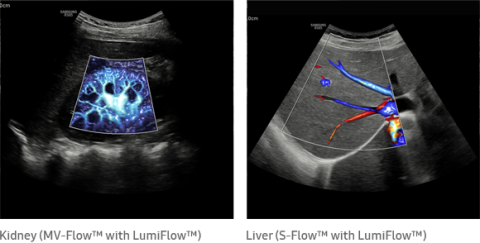

The color imaging performance has been improved to clearly visualize the hemodynamics of the blood flow. A greater sensitivity resulting from new color signal processing and a realistic 3D visualization of blood flow help understand the microcirculatory blood flows, accurate detection of peripheral blood vessels, and volumes of slow blood flows.

LumiFlow™ is a function that visualizes blood flow in three dimensional-like to help understand the structure of blood flow and small vessels intuitively.

MV-Flow™ visualizes microcirculatory and slow blood flow to display the intensity of blood flow in color. It is suitable for observation of microcirculatory blood flow and volume of slow blood flow.

The function uses directional power Doppler technology, enabling you to examine even the peripheral vessels. It displays information on the intensity and direction of blood flow.